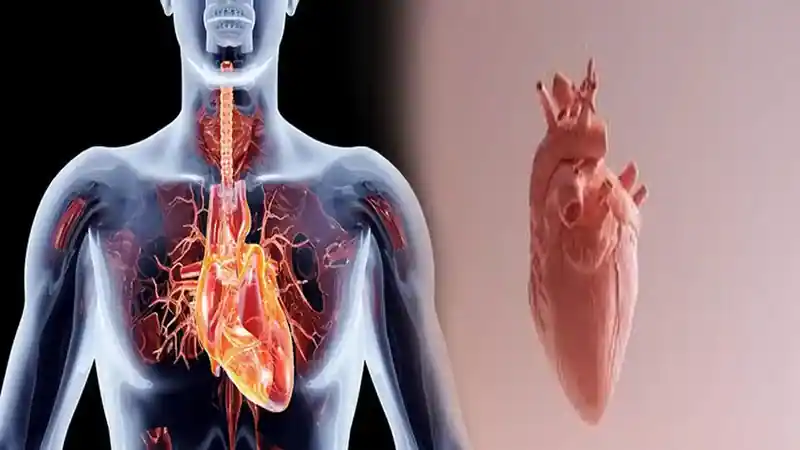

Jantung rematik, atau dalam istilah medis Rheumatic Heart Disease (RHD), adalah kondisi serius yang seringkali bermula dari infeksi yang terabaikan. Kondisi ini merupakan dampak jangka panjang dari demam rematik, yang merusak katup-katup jantung secara permanen. Memahami cara mengobati jantung rematik dan mengelolanya dengan tepat bukan hanya tentang pengobatan, tetapi tentang komitmen untuk menjaga kesehatan jantung seumur hidup.

Memahami Jantung Rematik: Dari Sakit Tenggorokan ke Kerusakan Jantung

Jantung rematik tidak muncul secara tiba-tiba. Ia adalah konsekuensi tragis dari perjalanan penyakit yang sebenarnya bisa dicegah. Mari kita telusuri prosesnya:

- Infeksi Awal: Dimulai dari infeksi tenggorokan atau demam scarlet yang disebabkan oleh bakteri Streptococcus pyogenes (Grup A Streptococcus).

- Respon Autoimun yang Salah: Pada sebagian orang, sistem kekebalan tubuh bereaksi berlebihan terhadap bakteri ini. Sayangnya, respons ini juga menyerang jaringan tubuh sendiri yang sehat—terutama pada sendi, kulit, otak, dan yang paling berbahaya: katup jantung.

- Demam Rematik: Reaksi autoimun inilah yang disebut demam rematik, ditandai dengan demam, nyeri dan bengkak sendi yang berpindah-pindah, ruam kulit, atau gerakan tubuh tak terkendali (Sydenham’s chorea).

- Kerusakan Permanen: Peradangan berulang dari demam rematik menyebabkan jaringan katup jantung menebal, membentuk jaringan parut, dan menyempit atau justru tidak dapat menutup rapat. Inilah yang akhirnya menjadi jantung rematik.